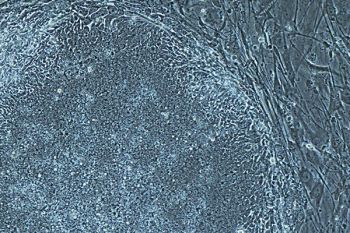

Buang Lemak Tubuh Berarti Buang Sel Punca

Konsultan sel punca, dr. Karina F. Moegni, SpBP-RE mengatakan, sebagai salah satu sumber stem cell, lemak mampu menyimpan stem cell paling banyak dan paling lama. Oleh karena itu, menurut dia, ...